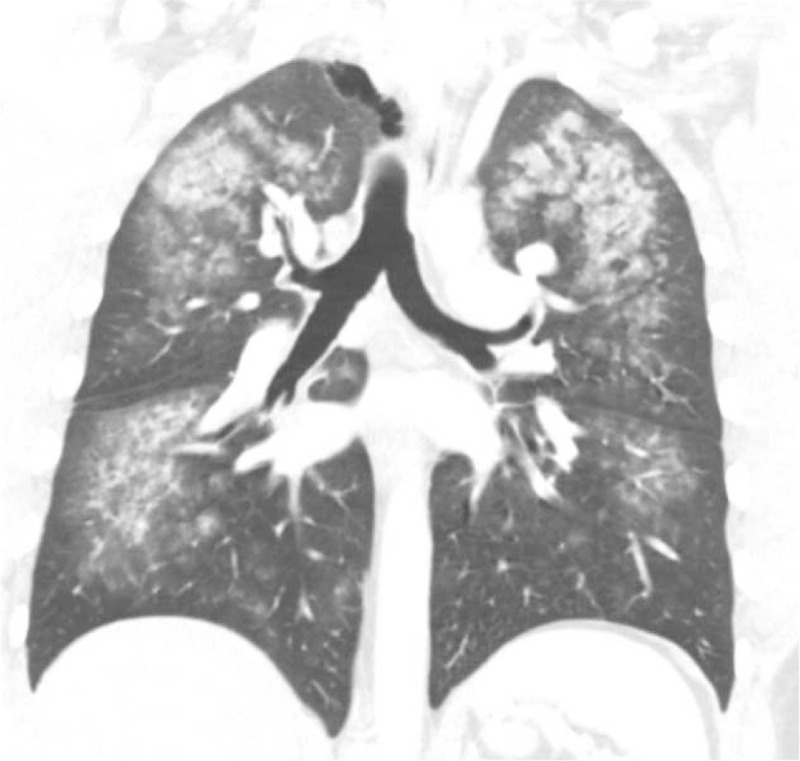

Chest radiograph (Figure 1A) showed increased interstitial markings and chest computed tomography (CT) scans (Figures 2 and 3) showed diffuse ground-glass opacities. An echocardiogram indicated a normal ejection fraction of 66% with no valvular abnormalities. A bronchoscopy with bronchoalveolar lavage (BAL) was initially bloody, but subsequently became clear (Figure 4). BAL cell counts showed leukocytes at 120 cells/mm3, with 98% neutrophils, and red blood cells at 28,250 × 106 cells/mm3. A transbronchial biopsy revealed chronic inflammation. The hemoglobin was 15.8 g/dl, coagulation profile was normal, vasculitis work up consisting of antinuclear antibody, rheumatoid factor, anti-DNA antibody, and antiglomerular basement membrane antibody was negative. The patient’s beta natriuretic peptide was 13 pg/ml and his urine toxicology was positive for cannabinoids.

Our case is unique as significant hemoptysis associated solely with marijuana use has not been reported. Evidence of chronic inflammation on transbronchial biopsy in this otherwise healthy male supports chronic effects of marijuana on the lung parenchyma. Radiographically and bronchoscopically, our patient appeared to have the source of injury at the level of distal bronchioles and/or alveoli. Future reports on this phenomenon will hopefully give greater insight into this rare association to better define the pathophysiological mechanism linking hemoptysis with inhalational marijuana use.